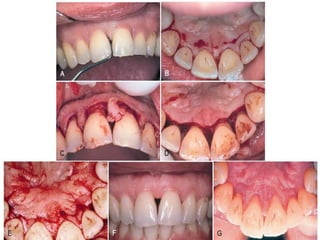

MODIFIED WIDMAN FLAP

▸ 1965 Morris - “unrepositioned mucoperiosteal flap”

▸ 1974 Ramfjord and Nissle described the same

procedure - “modified Widman flap”

▸ This technique offers the possibility of establishing an

intimate postoperative adaptation of healthy

collagenous connective tissue to tooth surfaces and it

provides access for adequate instrumentation of the

root surfaces and immediate closure of the area

▸ Step 1: The initial incision is an internal bevel incision to

the alveolar crest starting 0.5 mm to 1 mm away from

the gingival margin. Scalloping follows the gingival

margin

▸ Step 2: The gingiva is reflected with a periosteal elevator

▸ Step 3: A crevicular incision is made from the bottom of

the pocket to the bone in such a way that it

circumscribes the triangular wedge of tissue that

contains the pocket lining

▸ Step 4: After the flap is reflected, a third incision is made

in the interdental spaces coronal to the bone with a

curette or an interproximal knife, and the gingival

collar is removed

▸ Step 5: Tissue tags and granulation tissue are removed

with a curette. The root surfaces are checked and then

scaled and planed, if needed

▸ Step 6: Bone architecture is not corrected unless it

prevents good tissue adaptation to the necks of the

teeth. Every effort is made to adapt the facial and

lingual interproximal tissue adjacent to each other in

such a way that no interproximal bone remains

exposed at the time of suturing. The flaps may be

thinned to allow for close adaptation of the gingiva

around the entire circumference of the tooth and to

each other interproximally

▸ Step 7: Continuous, independent sling sutures are placed

in both the facial and palatal areas and covered with a

periodontal surgical pack